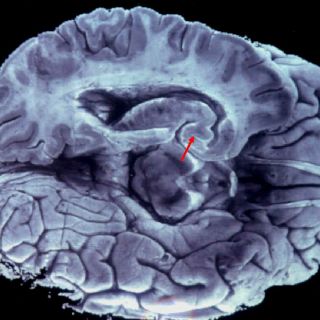

- Utilizamos sólo el 10 por ciento de nuestro cerebro. Esta teoría que se le ha atribuido infundadamente a Albert Einstein, es uno de los mitos más antiguos sobre nuestro cuerpo. De acuerdo al British Medical Journal (BMJ), investigadores han aclarado que la mentira surgió en 1907, para argumentar el potencial de las personas de desarrollar múltiples talentos. La verdad es que utilizamos el 100 por ciento de nuestro cerebro. Especialistas señalan que las imágenes de resonancia magnética y estudios del metabolismo cerebral, demuestran que durante el día no queda ninguna parte del cerebro sin ser activada. Lo importante es fomentar la actividad cognitiva y cerebral desde la infancia, porque eso mantiene y aumenta las conexiones cerebrales.